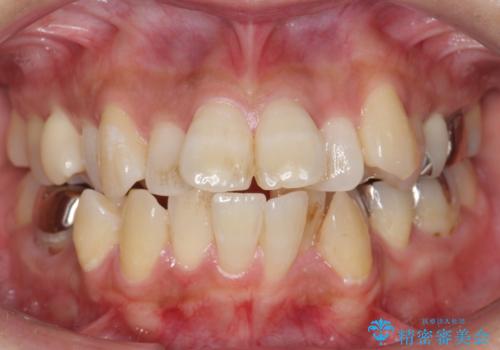

前歯のデコボコを改善 インビザライン矯正

担当医 藤巻太一朗